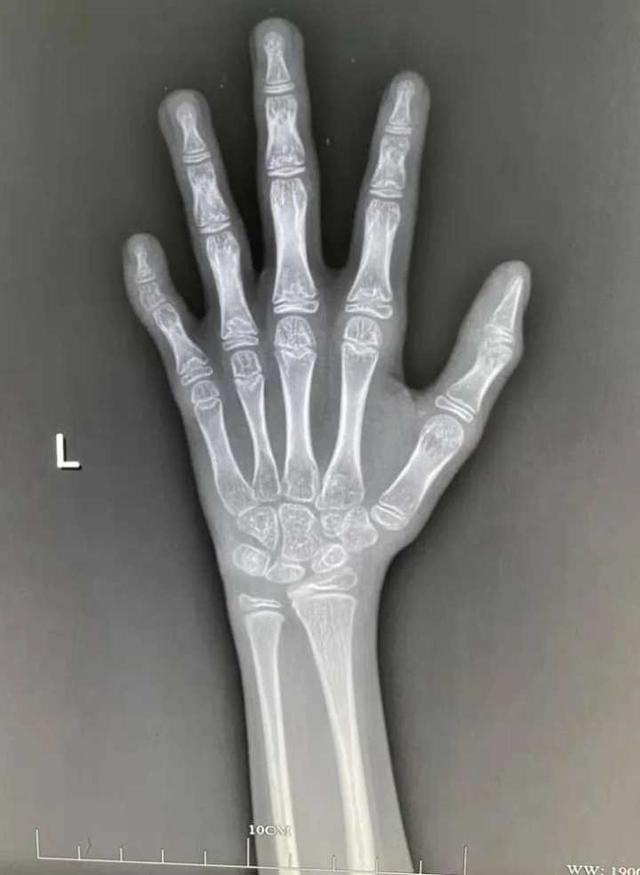

骨龄(bone age,BA)是骨骼年龄,一般指儿童及青少年骨骼发育水平。

很多父母误以为测骨龄较为麻烦,其实只需配合完成一次左侧腕关节正位X线光片拍摄即可。

拍完骨龄片后,医生一般会根据简单计数法、图谱法、评分法或者计算机骨龄评分系统等来评价(目前最常用的是G-P图谱法和TW3评分法)。